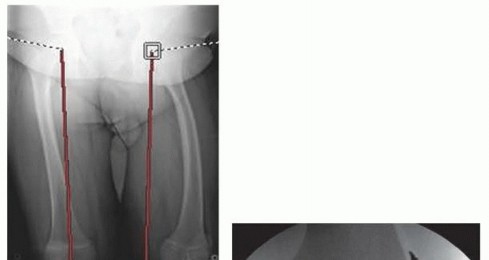

- FIG 2 • A. A 13-year-old girl with knee pain and difficulty with ambulation secondary to genu valgum. B. Standing AP radiograph of her lower extremities demonstrating bilateral genu valgum with abnormal LDFA bilaterally and an abnormal MPTA on the right tibia. She was indicated for bilateral medial distal femoral

- guided growth and right medial proximal tibia guided growth. C. Standing AP radiograph at 7 month postoperatively demonstrates normalization of her mechanical axis. (Courtesy of UW Pediatric Orthopaedics.)